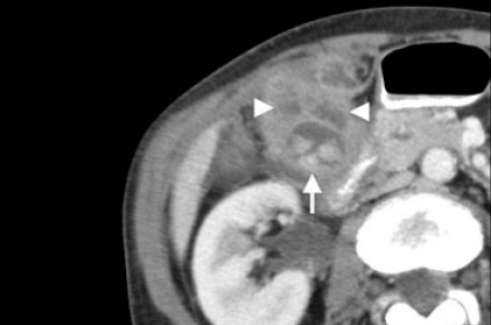

Выше представлено КТ пациента 71 года с ксантогранулематозным холециститом. Постконтрастное КТ. Визуализируется утолщение стенки желчного пузыря с включениями, которые соответствуют абсцессу или фокусам воспаления.